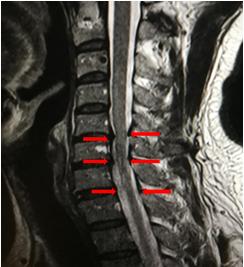

2019年3月7日19时,躺在核磁共振的检查台上,像是被关在密闭的笼子里,耳边是机器嗡嗡的轰鸣声,去枕平卧的检查姿势让我的颈部疼痛、右上肢麻木加重,肌肉不自主地抽动,15分钟下来右手仿佛不是自己的了,抬不起来。还是第一时间就让影像科老师帮我看了一下检查结果,第5、6、7椎间盘突出,神经根明显压迫(如图1红色箭头)。意料之中,但还是无法接受自己是个颈椎病病人的事实。